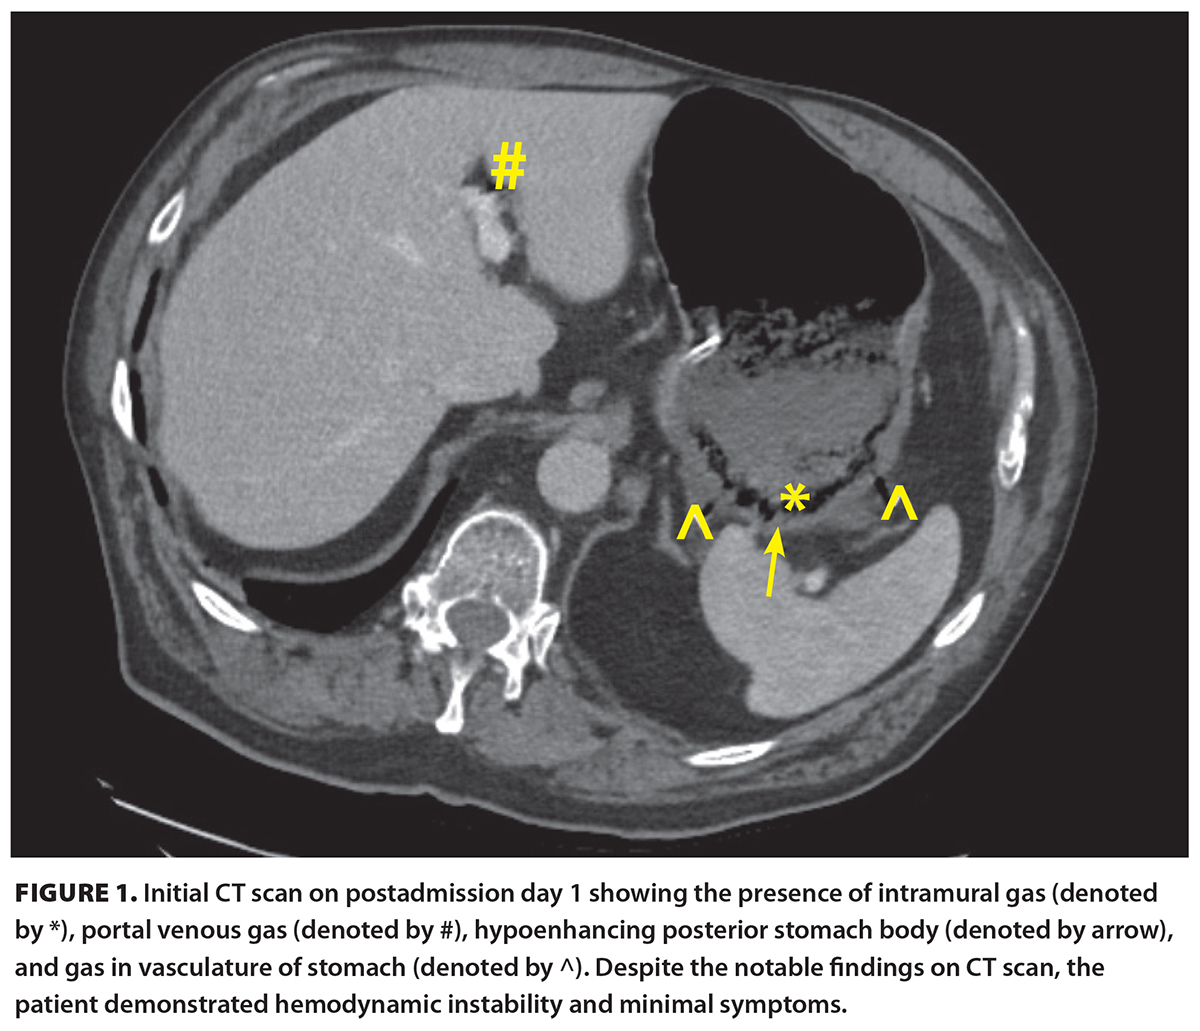

A 71-year-old male presented to a peripheral centre with chest pain and shortness of breath after a low-velocity motor vehicle accident. His medical history was significant for previous myocardial infarction with stents in situ, hypertension, dyslipidemia, gastroesophageal reflux disease, and chronic obstructive pulmonary disease. He had an 80-pack-year smoking history and was otherwise functionally independent. Cardiac workup was negative, and he was presumed to have a chronic obstructive pulmonary disease exacerbation. A CT scan of the abdomen was performed [Figure 1] in the context of the recent motor vehicle accident and new chest pain. Incidentally, the CT showed hypoenhancement of the posterior gastric wall with intramural air, gas extending along the right and left gastroepiploic veins, and portal venous gas. There was adjacent inflammation without any significant free fluid.